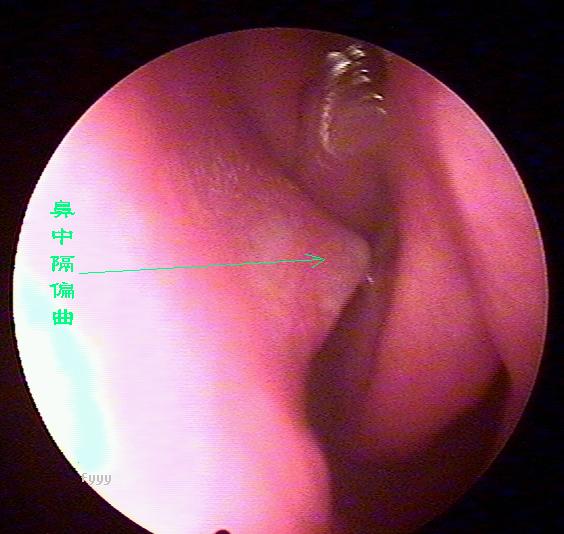

鼻内窥镜下的鼻中隔偏曲

鼻中隔偏曲进行鼻内检查以判断鼻中隔偏曲的类型和程度,注意鉴别鼻中隔粘膜肥厚和是否同时存在鼻内其它疾病,如原发病变—肿瘤、异物或继发病变—鼻窦炎、息肉等。 另一罕见者为鼻中隔梅毒瘤,其质地中亦较硬,但该处粘膜明显充血。

“狼牌内窥镜”可通过耳鼻咽喉等部位狭小通道直接看到常规仪器检查所不能看到的病灶,并可放大数十倍甚至百倍,有助于清晰而详细地观察到周围的病变,只需要5分钟即可检测出疾病病因,辅助医师进行精准治疗,告别耳鼻咽喉疾病治疗误区,具有不易漏诊而精准治疗的优点,被业界称为耳鼻喉科医生的“只眼睛”。